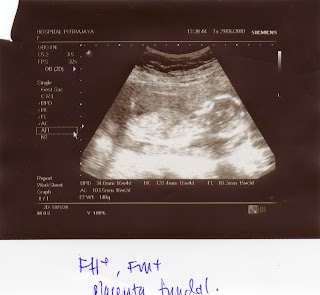

rasenya tue jea cite baby buat mase nie sbb baby blum besar sgt...kat bwh nie gmbr2 scan hari tue...hehehe